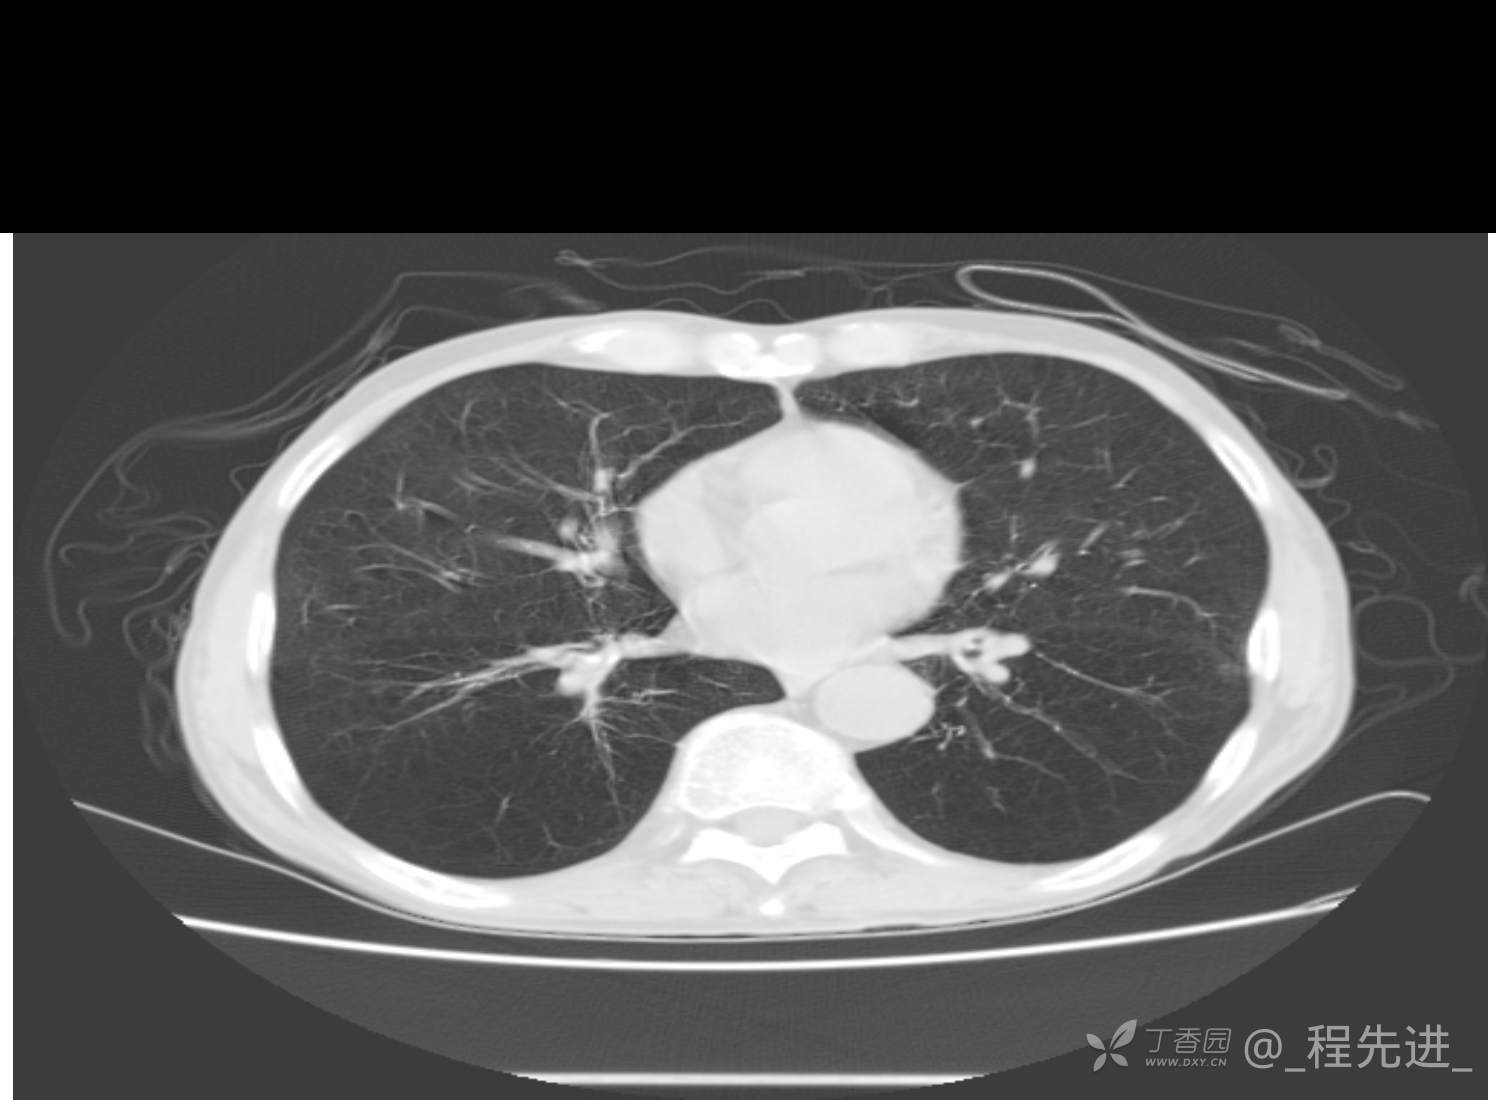

患者性别:男

患者年龄:81岁

简要病史:反复咳嗽、咳痰20余年,加重1周。两肺呼吸音低,可闻及散在干湿啰音。